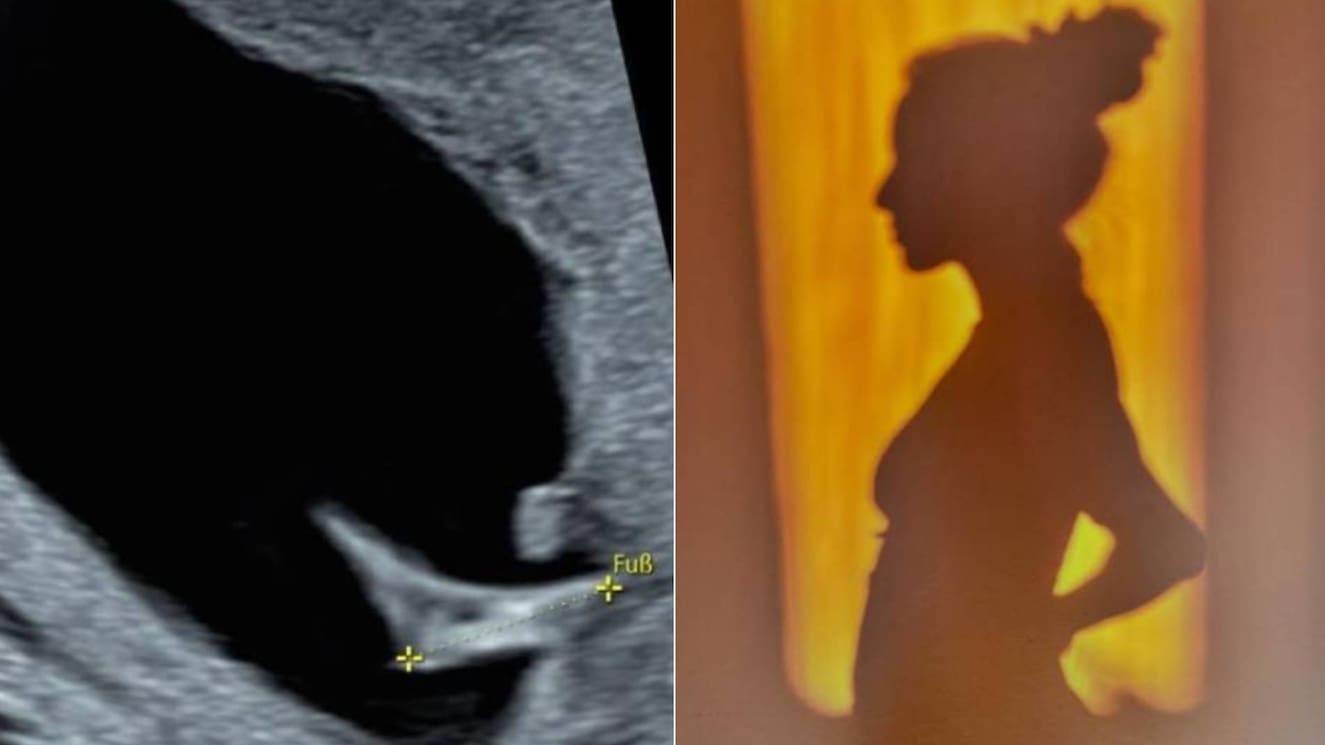

Sin embargo, hay un tema que afecta profundamente a la participante de Fiebre de Baile y es su lucha por ser mamá:

“Creo que Dios y la vida me están castigando, porque siempre dije que no quería ser mamá. Desde niña nunca me vi casada y con un hijo. Siempre me vi con mi familia en otro país y haciendo lo que estoy haciendo ahora. Pero nunca fue mi prioridad.

“Entonces, en ese afán me puse demasiado anticonceptivos. Era tanto el trauma de que no quería ser mamá que yo tenía el Implanon y además me ponía inyecciones. Entonces, cuando con mi pareja dijimos ‘vamos a ser papás’, empecé con la desesperación porque para mí era muy normal que no me cayera el periodo en años”.

“Todavía no he llegado a esa parte (de hacer tratamiento de fertilización), porque no es que me han dicho ‘tú no puedes ser mamá’. El tema que me están haciendo ahora es detox, limpiar el cuerpo.

“Pero el tema que me tiene mal, porque si bien no me cae el periodo, siempre cuatro días al mes me pongo súper mal. Me dan síntomas como si fuera a parir, porque me dilato. Entonces la primera vez que fui dije ‘yo creo que estoy embarazada y que tengo un embarazo ectópico’.

“Me dijeron ‘no pasa nada, es parte del proceso’. Pero es mucho dolor, mucho vómito, no me dan deseos de comer; me pongo muy mal y, son tantos los dolores, que me dan unas pastillas, pero esas pastillas me hacen dormir todo el día”.